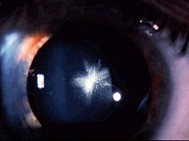

许多先天性白内障患者,(如图),常合并其他眼病或异常,如()

-

男性,79岁,双眼视物模糊4年余,裂隙灯检查如图,双眼还可能出现的症状有哪些()